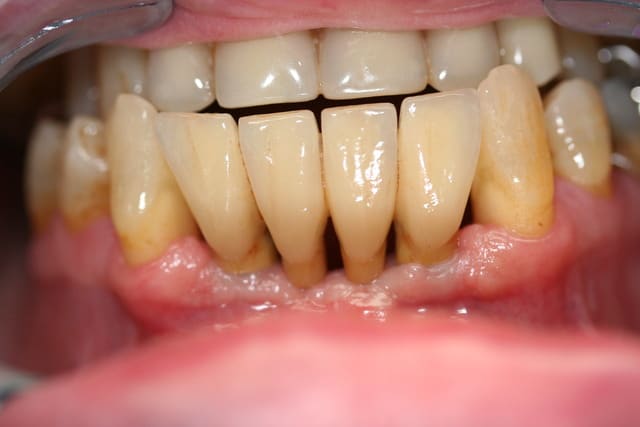

dentiste57

01/07/2009 à 22h45

hi hi

j'en ai un du même genre...

faut quand même que je lui dise de brosser un peu plus.

Bravo pour le prothésiste, il a bien imiter la paro...

''C'est que quand je brosse docyeur, mes gencives saignent, alos ça doit pas être très bon la brosse...''

Brosser un peu plus que pas brosser serait déjà mieux...